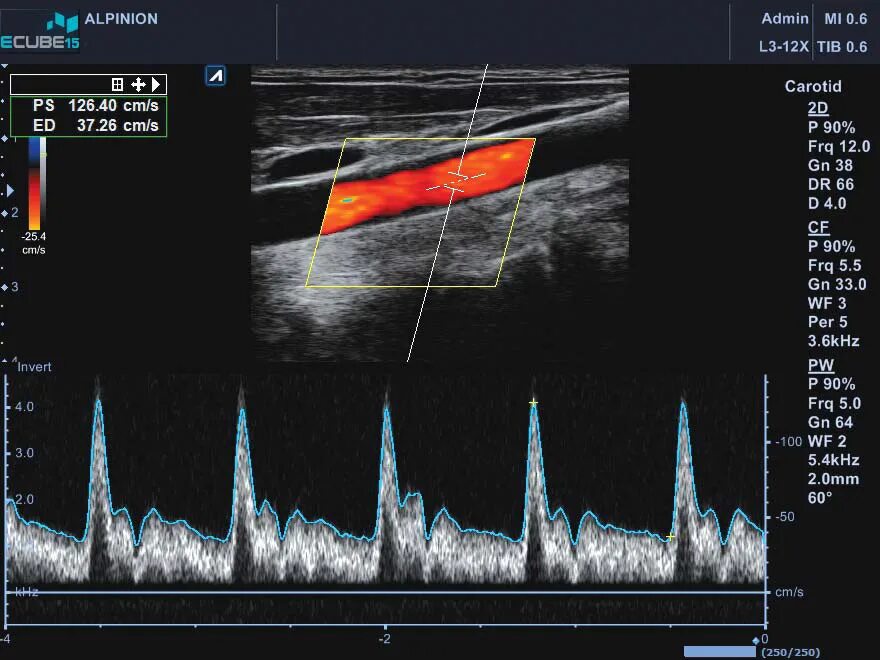

Режимы узи аппарата